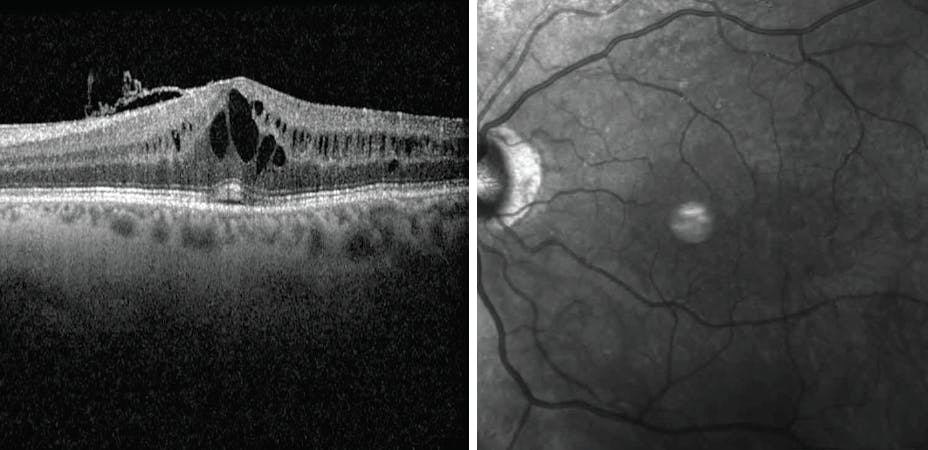

On examination, VA was 20/30 OS, with normal IOP and CME noted on OCT (Figure 1). There were no signs of macular degeneration, retinal vascular disease, or uveitis, only the previously noted mild epiretinal membrane. In addition, the timing of the vision decrease, the unilateral CME, and onset of prostaglandin use in the same eye (not bilaterally) was suggestive of a causal relationship.

<p>Figure 1. OCT shows CME related to latanoprost administration.</p>

Figure 1. OCT shows CME related to latanoprost administration.